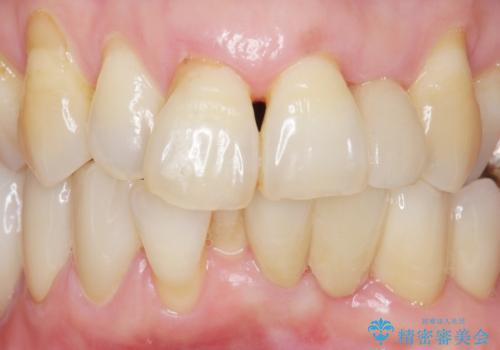

気にされていた前歯と奥歯の動揺がなくなったことと自然な仕上がりに喜んで頂けました。

クラウンの種類:オールセラミッククラウン スタンダード